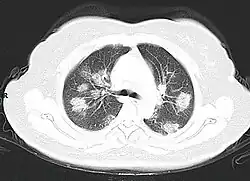

Séquelles pulmonaires

Comme pour la plupart des survivants du syndrome de détresse respiratoire aiguë, la dyspnée est le symptôme persistant le plus courant après un Covid-19 grave, avec une prévalence de 42 à 66 % après plus de 60 jours de suivi. Par exemple, parmi 1800 patients espagnols qui ont dû subir une trachéotomie au cours d'un épisode aigu, seuls 52 % ont réussi à être sevrés de la ventilation mécanique un mois plus tard. Cela s'explique par une baisse de la capacité de diffusion pulmonaire (la quantité de gaz absorbé par le sang des capillaires pulmonaires à partir du gaz alvéolaire), phénomène déjà observé chez des survivants de la grippe H1N1. L'invasion des cellules alvéolaires par le SRAS-CoV-2, ou l'inflammation périvasculaire, participent à la rupture des barrières endothéliales et épithéliales avec invasion de monocytes et de granulocytes neutrophiles et extravasation d'un blastème riche en protéines[49],[50],[51],[52],[53].

Par ailleurs, environ 40 à 50 % des Covid-19 asymptomatiques pourraient présenter des anomalies radiographiques des poumons, le plus souvent des nodules en verre dépoli[54],[55]. Le verre dépoli aigu exprime un œdème, une hémorragie ou simplement une inflammation pulmonaire. Généralement il faut moins de 3 mois pour que ces nodules disparaissent[56].